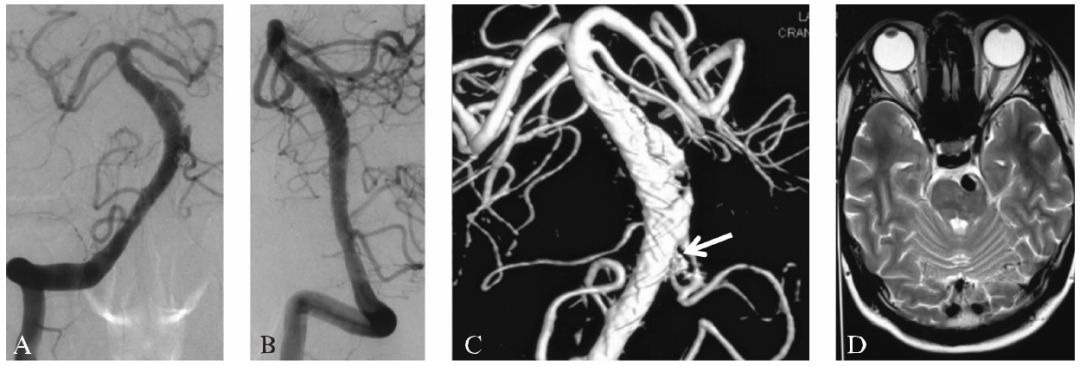

首次术后24个月DSA随访提示病变形态较前改善,但仍有部分管腔膨出,并向穿支动脉供血(图16-5A~C)。临床随访28个月,症状无复发,复查MRI未见新发脑干梗死(图16-5D)。

图16-5首次术后24个月DSA和28个月MRI复查

A:DSA(前后位)复查提示病变形态进一步改善,仍有少量支架外管腔存在,并向穿支动脉供血;

B:DSA侧位像造影;

C:三维重建后显示的支架外管腔及其供应的穿支动脉(白色箭头);

D:首次术后28个月复查MRI显示未见明显脑干梗死(T₂WI轴位)